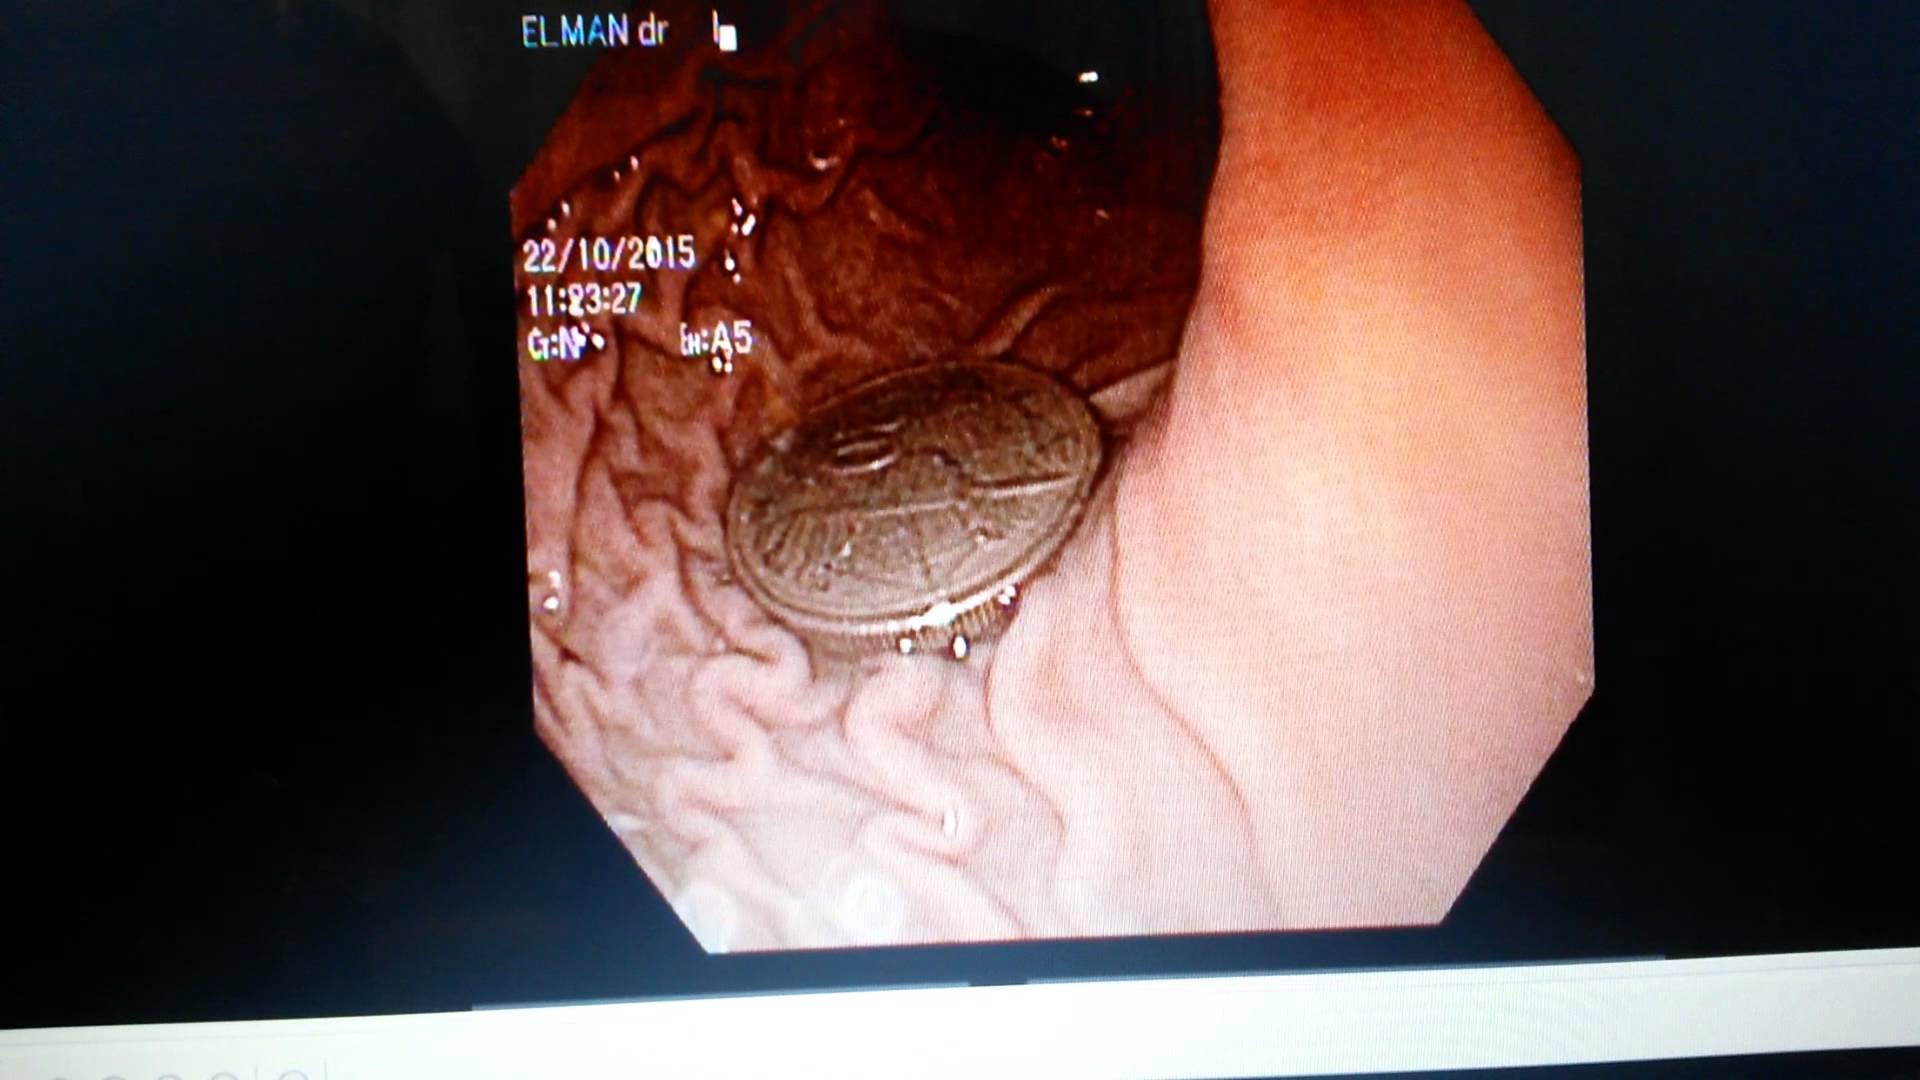

Respublika Müalicəvi Diaqnostika Mərkəzinin (RMDM) həkim-mütəxəssisləri tərəfindən bir neçə gün əvvəl RMDM-ə yad cisim udması, qusma, ürəkbulanma və halsızlıq şikayətləri ilə müraciət edən 4 yaşında uşaqda aparılan Rentgen müayinəsi zamanı mədədə yad cismin olması təsdiq edilib.

Səhiyyə Nazirliyindən verilən məlumata görə, müayinənin nəticəsində yad cismin endoskopik yolla xaric edilməsinə qərar verilib.

RMDM-in həkim-ümumi cərrahı İbrahim Əfəndiyev, həkim-qastroenteroloq Cəmil Kamilli və həkim-anestezioloq Rasim Əliyevin birgə səyi nəticəsində yad cismin xaric edilməsi fəsadsız başa çatdırılıb və uşaq tam sağlam vəziyyətdə evə yola salınıb./azvision.az